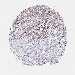

OVARIAN CANCER - Protein expressioni

A mouse-over function shows sample information and annotation data. Click on an image to view it in a full screen mode. Samples can be filtered based on level of antibody staining by selecting one or several of the following categories: high, medium, low and not detected. The assay and annotation is described here.

Note that samples used for immunohistochemistry by the Human Protein Atlas do not correspond to samples in the TCGA dataset.

Antibody stainingi

Antibody staining in the annotated cell types in the current human tissue is reported as not detected, low, medium, or high, based on conventional immunohistochemistry profiling in selected tissues. This score is based on the combination of the staining intensity and fraction of stained cells.

Each image is clickable and will lead to virtual microscopy that enables deeper exploration of all samples and also displays staining intensity scores, fraction scores and subcellular localization as well as patient and tissue information for each sample.

Antibody HPA035568

Antibody HPA037017

Cystadenocarcinoma, serous, NOS

Carcinoma, endometroid

Cystadenocarcinoma, mucinous, NOS

Carcinoma, NOS